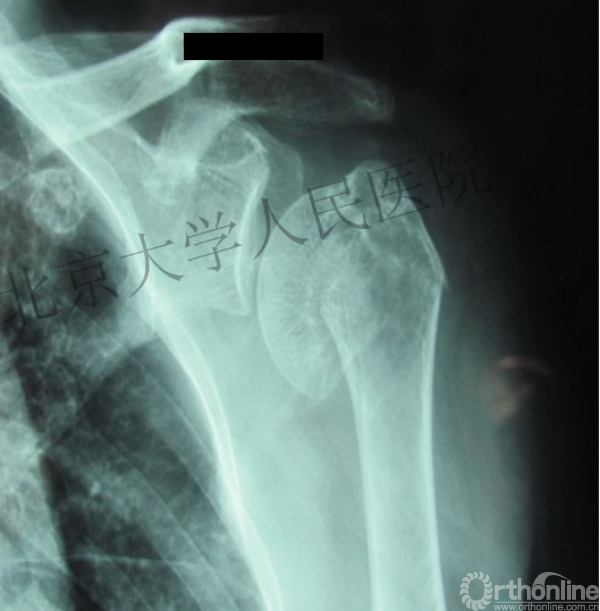

内侧皮质粉碎,低位外科颈骨折,肱骨头-干角维持困难。

术后复位丢失,肱骨头内翻畸形。

能否该偏心固定(钢板)为髓内固定,增加力臂?

此时对比髓内钉是不是有很大优势?